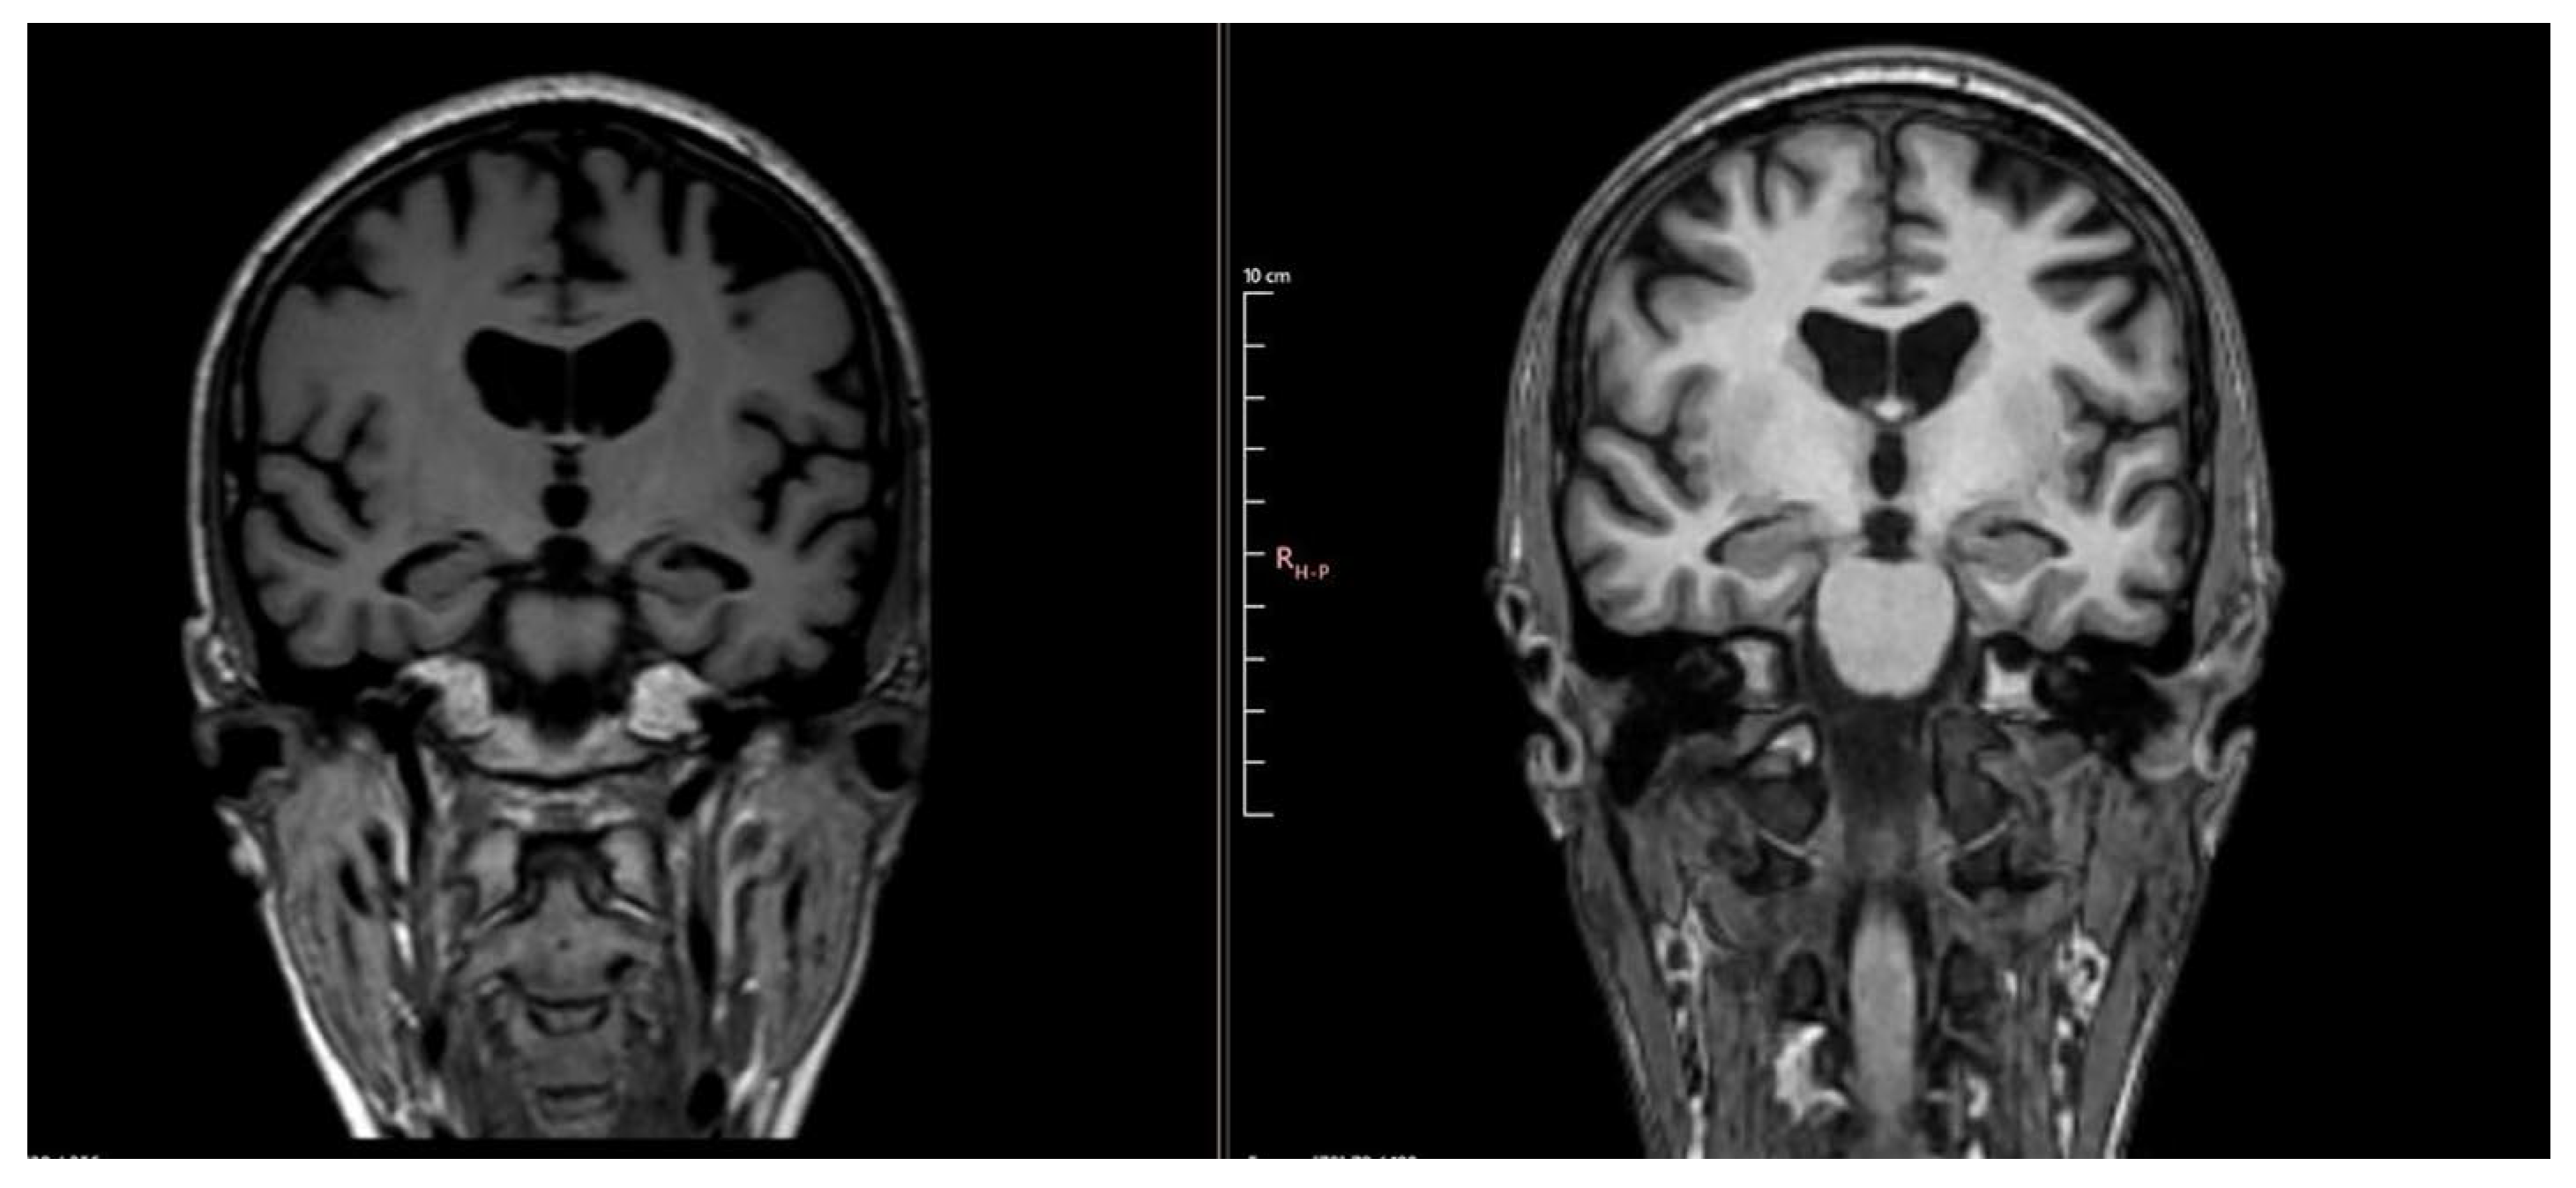

| Year 3 (1 year ago) | MMSE 9/30, MoCA 4/30 | Tau ↑ 877 pg/mL; p-Tau ↑ 63.6 pg/mL; Aβ42 ↓ 0.94 | Hippocampal atrophy (MTA score 2); parietal atrophy (Koedam 2); severe corpus callosum thinning with splenium demyelination (T2/FLAIR hyperintensity, T1 hypointensity) | Severe cognitive disorder requiring permanent care; anxiety and depression prominent |

| Year 4 (Current) | Severe impairment, no formal testing | Not repeated | Global progression of atrophy; no new lesions | Severe apathy, hypersomnia, total dependence, high wandering risk |